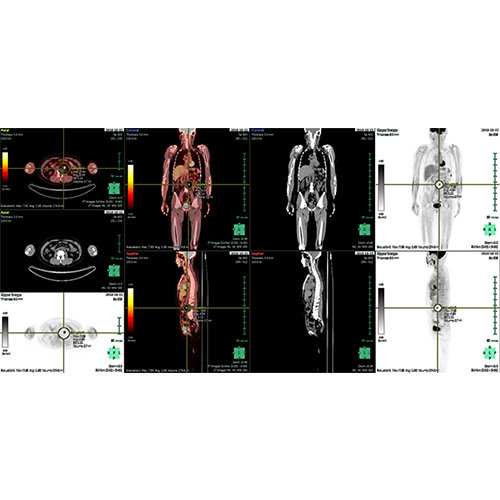

High-quality and fast 3D reconstruction and 3D rendering

Performs 3D reconstruction and volume rendering.

Multi-planar slicing.

Axis-aligned cropping with context.

Side-by-side comparative assessment for pre- and post-operative scans.